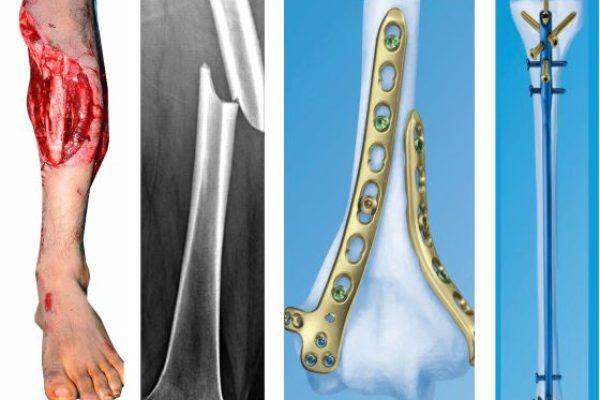

Joint pain, fractures, and sports injuries can limit your ability to live fully. At SALAM Shah Alam Specialist Hospital, our Orthopaedics & Traumatology team is here to help you move better—whether you’re recovering from an injury or managing a long-term condition.

This specialty focuses on the bones, joints, ligaments, muscles, and tendons. From diagnosing pain to performing surgery or rehabilitation, our goal is to get you back on your feet with minimal discomfort and long-term relief.